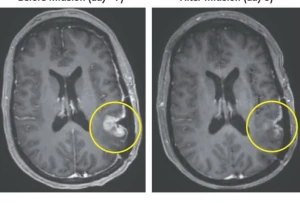

بالفيديو: قصة رجل أصيب بالجلطة مرتين بسبب زوجته.. وأخصائي نفسي يكشف عن نصيحة أبعدته عن الإصابة بالثالثة